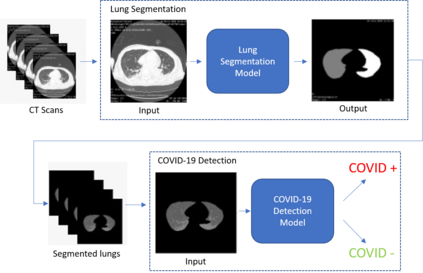

COVID-19 infection caused by SARS-CoV-2 pathogen is a catastrophic pandemic outbreak all over the world with exponential increasing of confirmed cases and, unfortunately, deaths. In this work we propose an AI-powered pipeline, based on the deep-learning paradigm, for automated COVID-19 detection and lesion categorization from CT scans. We first propose a new segmentation module aimed at identifying automatically lung parenchyma and lobes. Next, we combined such segmentation network with classification networks for COVID-19 identification and lesion categorization. We compare the obtained classification results with those obtained by three expert radiologists on a dataset consisting of 162 CT scans. Results showed a sensitivity of 90\% and a specificity of 93.5% for COVID-19 detection, outperforming those yielded by the expert radiologists, and an average lesion categorization accuracy of over 84%. Results also show that a significant role is played by prior lung and lobe segmentation that allowed us to enhance performance by over 20 percent points. The interpretation of the trained AI models, moreover, reveals that the most significant areas for supporting the decision on COVID-19 identification are consistent with the lesions clinically associated to the virus, i.e., crazy paving, consolidation and ground glass. This means that the artificial models are able to discriminate a positive patient from a negative one (both controls and patients with interstitial pneumonia tested negative to COVID) by evaluating the presence of those lesions into CT scans. Finally, the AI models are integrated into a user-friendly GUI to support AI explainability for radiologists, which is publicly available at http://perceivelab.com/covid-ai.